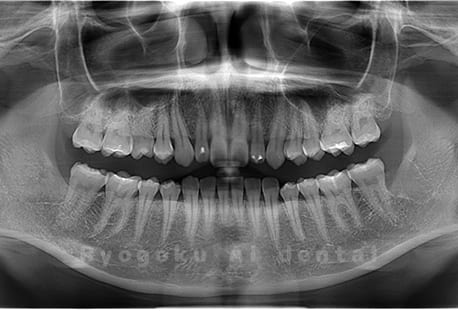

水平埋伏の親知らず

歯茎の中で完全に横に生えてしまうタイプです。

この親知らずを水平埋伏智歯と言います。このタイプはほとんどが下顎のケースです。真横に生えているので抜歯の際は難易度が高く2~3つに砕いて分けて抜歯をします。